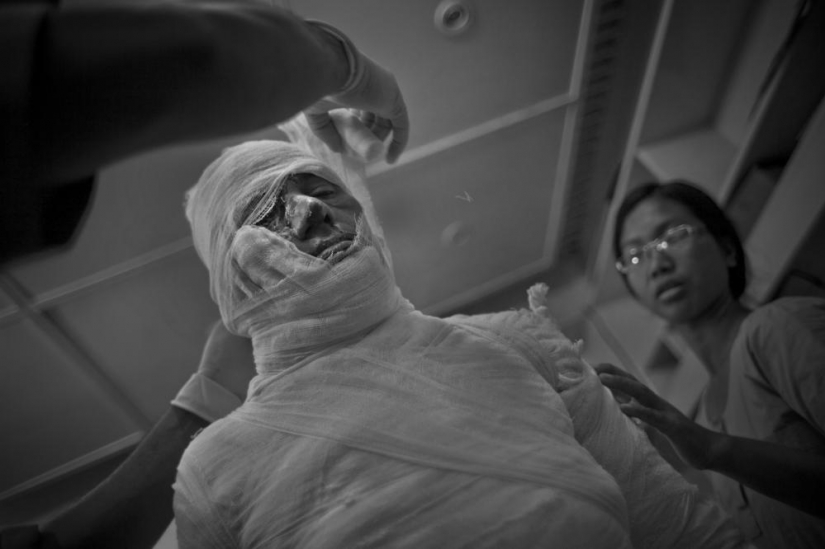

4. Este 60 años de edad, la mujer se roció con ácido sobre una disputa de tierras. Ella recibió quemaduras en el 65% de la superficie de la piel. Fotógrafo: Khaled Hasan

5. El ácido corroe los tejidos e incluso los huesos. Muy a menudo daña permanentemente los ojos y los oídos. Muchas de las víctimas necesidad de ir a través de docenas de cirugías plásticas para ser capaz de vivir normalmente más. Financiación o patrocinio de la industria, y la mayoría de las víctimas de las zonas rurales, y el dinero para la cirugía de que simplemente no tienen. Ellos permanecerán desfigurado de por vida, y sólo unos pocos serán capaces de casarse. Fotógrafo: Khaled Hasan

9. El mundo ve en estas mujeres víctimas, pero rara vez de suicidarse. Se someten a muchas de las operaciones para la restauración de la nariz, para restaurar la visión y el tratamiento de quemaduras. Ellos creen que la quiebra puede ser reparado. Fotógrafo: Khaled Hasan

14. Después de 15 días de matrimonio, el esposo Kalpana la puso sobre el umbral, como ellos querían más dote. Se exigió a los $ 3,000 que su familia no era simple. Nueve meses más tarde, sintiéndose ofendido, se fue a su casa y a la fuerza derramado en su boca ácido. Hoy, después de numerosas operaciones, Calpan puede hablar. Fotógrafo: Khaled Hasan